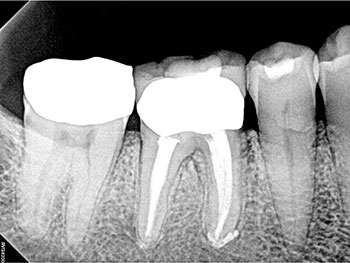

After the buildup and root-filling material were removed, a microscope was used to confirm that no cracks were present in the pulp chamber or the coronal third of the canals. This tooth was treated in multiple visits using calcium hydroxide, an antimicrobial intracanal medicament, and to confirm healing. The root canal system was cleaned, calcium hydroxide was placed, and a double-layered long-term provisional restoration made of Cavit and bonded composite were placed to seal the access preparation.

The patient returned in three months, when resolution of symptoms, healing of the deep probing defect and bone regeneration were confirmed. The tooth was obturated, and a foundational restoration was placed before the rubber dam was removed. Fourteen years of follow-up confirmed long-term periradicular health. The amount of appreciation and gratitude that this patient expressed reminds us that each individual tooth demands our best efforts.

Fig. 2: Postoperative PA.